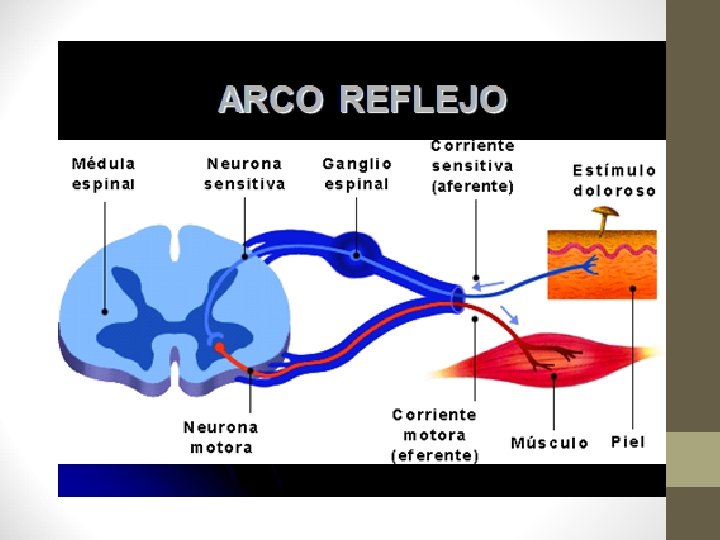

Cumple una Función conductora (sustancia blanca) y una Función elaboradora de reflejos (sustancia gris)